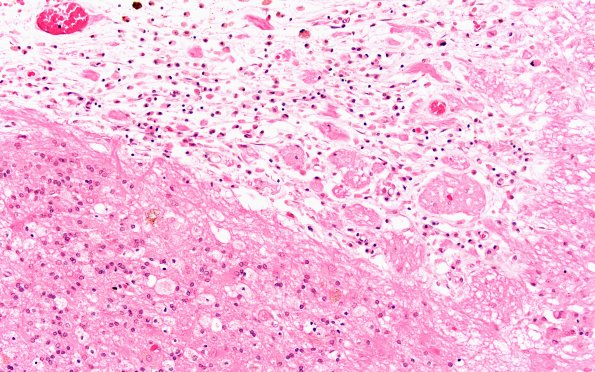

Washington University Experience | TRAUMA & FORENSIC | Contusions | 19A4 (Case 19) Contusion 20X

Higher magnification shows loss of neurons, astrocytosis, glial fingers and macrophages with hemosiderin (mostly in the adjacent cystic area) and lipid laden macrophages within the residual gliotic cortex. (H&E)